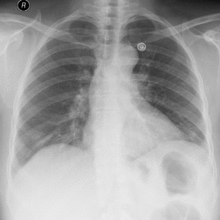

Si definisce pneumotorace la presenza di aria nello spazio pleurico con collasso parziale o totale dei polmoni. Classificazione dello pneumotorace pneumotorace spontaneo: compare spontaneamente, senza un rapporto di causa effetto, e può essere primitivo o secondario ad altre patologie. pneumotorace post-traumatico: può essere chiuso o entrante. Nello pneumotorace entrante, come abbiamo visto, c’è una […]